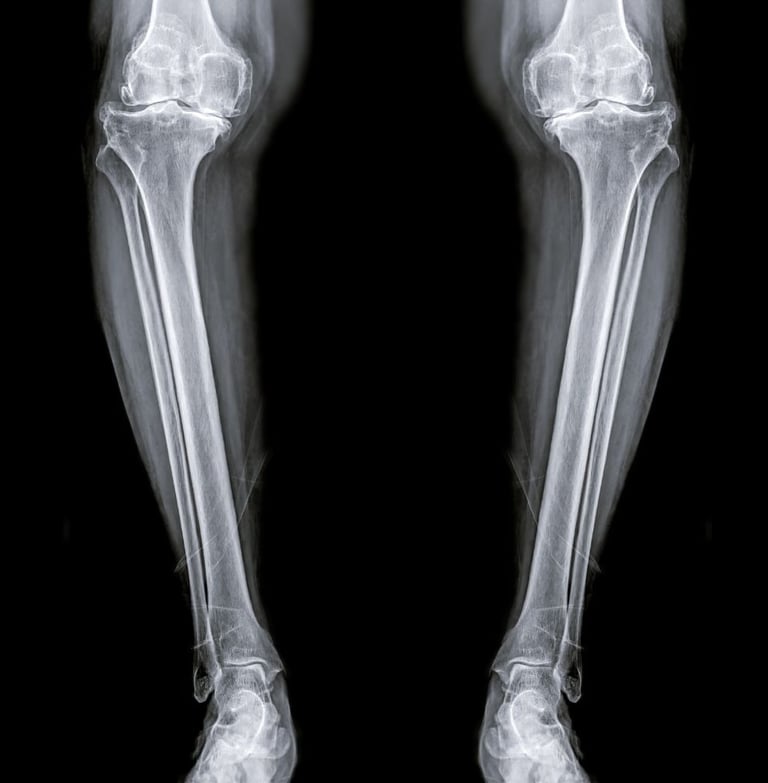

Diz kireçlenmesi, tıbbi adıyla osteoartrit, özellikle 50 yaş üstü bireylerde hareket kısıtlılığının ve kronik ağrının en büyük nedenlerinden biridir. Dizdeki kıkırdak dokusunun zamanla aşınmasıyla ortaya çıkan bu durum, "yaşlılık hastalığı" olarak bilinse de günümüzde yanlış beslenme ve hareketsizlik nedeniyle daha erken yaşlarda da görülmektedir.

Peki, her diz kireçlenmesi mutlaka protez ameliyatı ile mi sonuçlanmalıdır? Hayır. Günümüzde cerrahiye gerek kalmadan diz sağlığını koruyan ve ağrıları dindiren pek çok yenilikçi yöntem mevcuttur.